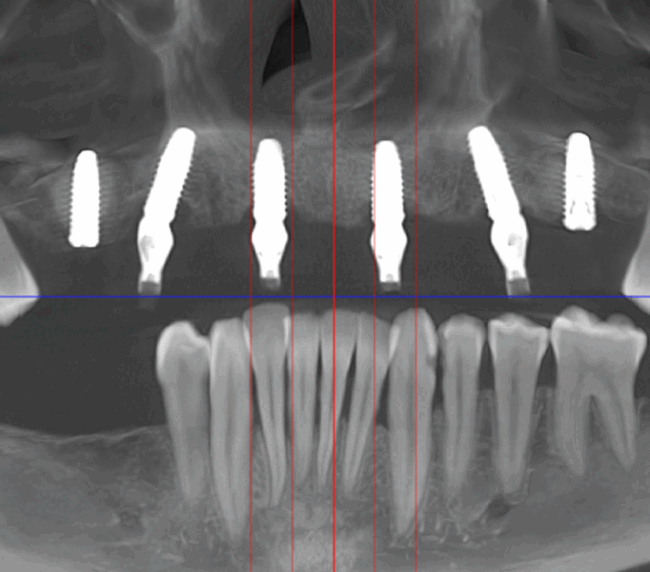

- Investigație imagistică completă, ideal CBCT (computer tomografie);

Metoda All-on-6 presupune inserarea chirurgicală a șase implanturi plasate strategic, pentru a asigura o proteză fixă stabilă și durabilă. Spre deosebire de conceptul All-on-4, recomandat în special pacienților cu deficit osos în zonele laterale ale maxilarului, All-on-6 are indicații mai largi și poate fi utilizat la majoritatea categoriilor de pacienți.

Această metodă este indicată pacienților cu edentație totală sau cu lipsuri dentare multiple, când dinții rămași nu mai pot susține o proteză fixă eficientă. Procedura se desfășoară în două etape:

- A doua etapă are loc la aproximativ 6 luni după intervenție, când se realizează proteza definitivă, care este fixată pe implanturi prin intermediul unor piese numite multiunit-uri. Această etapă presupune lucrul la nivelul multiunit-urilor, nu direct pe implanturi, reducând astfel riscul de complicații.